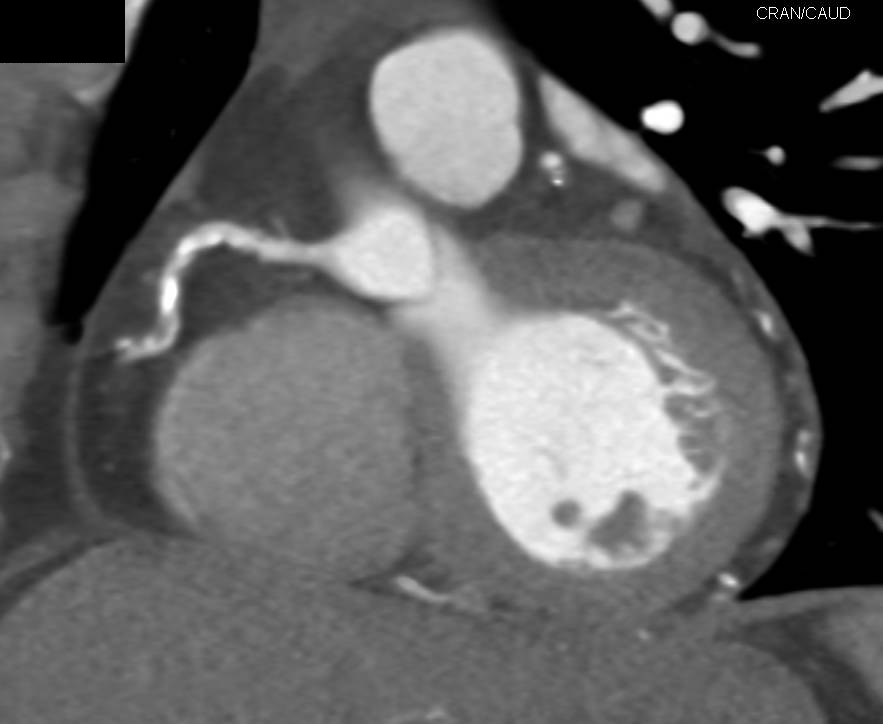

Aortic Valve Replacement (AVR)